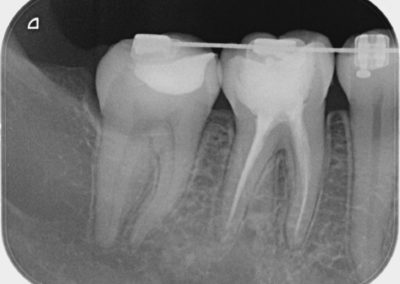

• Técnica bite wing